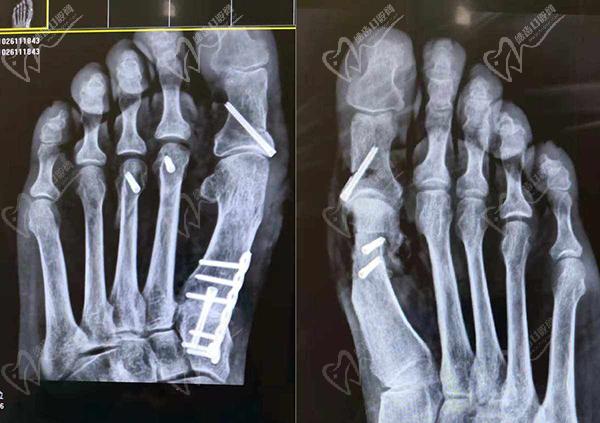

大腳骨微創(chuàng)手術:適合輕中度大腳骨外翻,蘇敬達大腳骨手術切口僅需要3-5個mm就可以做手術,能同時達到祛骨贅、復位關節(jié)、調整關節(jié)囊、收緊韌帶、截骨內推、家長足底力線等問題,確保手術不會復發(fā)。

大腳骨傳統(tǒng)手術:適合重度大腳骨外翻或合并癥